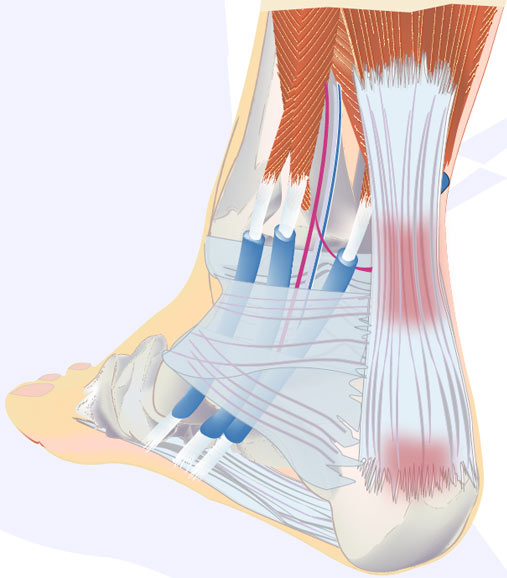

pictures of achilles tendon

Achilles Tendon Diagram – 1000+ images about medical anatomy on …

Musculare hi-res stock photography and images – Alamy

Transverse section of the Achilles tendon (midportion) region. Relation …

The Twisted Structure of the Achilles Tendon